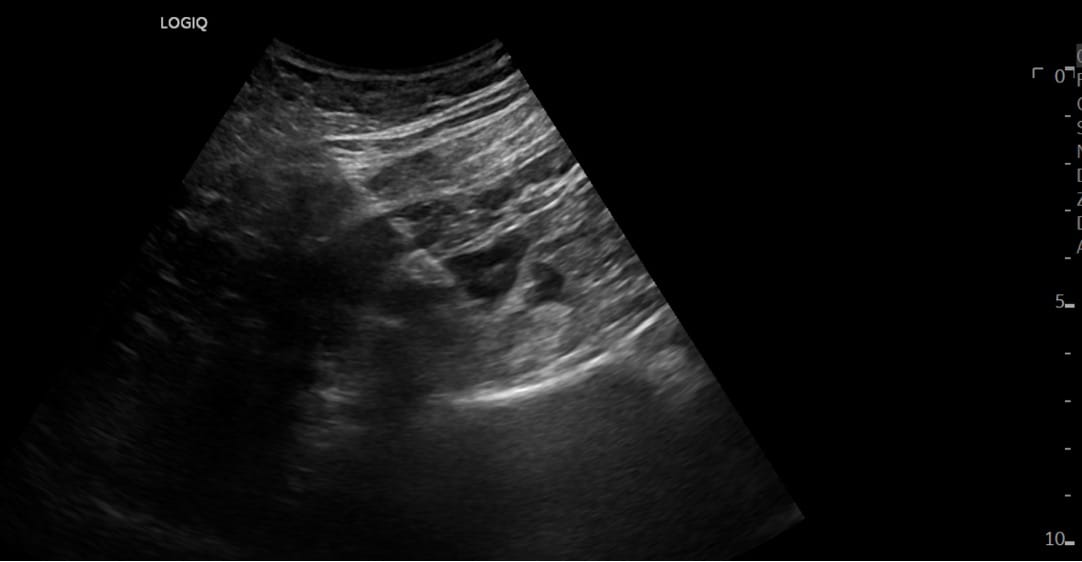

After optimal sonoanatomy is obtained, a 1% lidocaine skin wheal (2-3 mL) is administered next to the posterior edge of the ultrasound probe. Under real-time ultrasound guidance, an appropriately sized needle (We use an echogenic 21G stimulating needle at least 100 mm in length for single injection blocks and a 17 Ga Tuohy needle and a 19 Ga catheter for continuous regional anesthetic blocks.) connected to a peripheral nerve stimulator is inserted at the posterior edge using an in-plane approach. We use a posterior transversal approach, where the needle is inserted along the transverse process in order to avoid lumbar arteries and veins, as most often the lumbar arteries and veins are inter-transversal.2 The needle is advanced using nerve stimulation (see “nerve stimulation” below) until the tip is seen lateral to the lumbar plexus nerves (Figure 4 and Video).